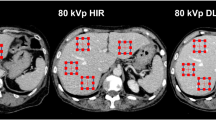

All patient datasets investigated were successfully processed by the evaluated AS software. Two representative patient datasets and their AS contours are shown in Figs. 1 and 2. As an example, the OARs in Fig. 1, esophagus, heart, liver, and spinal cord, were scored 2, kidneys and lungs received a qualitative score of 1. The DSCs were 0.98 for both lungs, 0.86 for the heart, and 0.56 for the spinal cord.

Depiction of manually and automatically generated contours of one representative dataset. Manual contours of esophagus, kidneys, lungs, liver, spinal cord, and trachea on the left side and automatic segmented structures on the right side in axial, coronal, sagittal and three-dimensional model view. The heart is segmented additionally, the missing right kidney was a segmentation failure with DSC = 0, HD = 50 mm, and qualitative score = 3. DSC Dice similarity coefficient, HD Hausdorff Distance